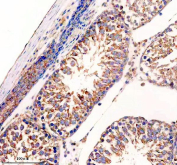

Immunohistochemistry analysis of UPF1 / Up-frameshift suppressor 1 antibody in human testis cancer tissue. FFPE human testis carcinoma shows cytoplasmic HRP-DAB brown staining in tumor cells, consistent with UPF1 expression. Positive staining is predominantly cytoplasmic with variable intensity among malignant cells, while nuclei are counterstained blue. Adjacent stromal and non-neoplastic elements demonstrate comparatively weaker signal. Heat induced epitope retrieval was performed by boiling tissue sections in EDTA buffer, pH 8.0, for 20 minutes followed by cooling prior to immunostaining.